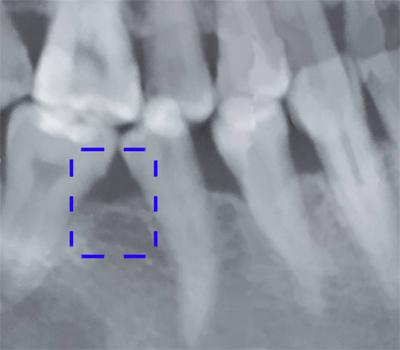

ภาพแสดงฟันล้มเข้าหาช่องว่างจากการสูญเสียฟันกรามและเกิดช่องห่างในฟันซี่ข้างเคียง

ภาพแสดงฟันล้มเอียงเนื่องจากการสูญเสียฟันกรามไปนาน

เมื่อสูญเสียฟันซี่ใดซี่หนึ่ง จะเป็นฟันกรามใหญ่ ฟันกรามน้อย หรือฟันหน้าก็ตาม ฟันที่อยู่ด้านข้างจะล้มเอียงเข้าหาช่องว่าง ทำให้เกิดฟันห่างในตำแหน่งใกล้เคียง ในขณะที่ฟันคู่สบด้านบนอาจยื่นยาวเข้าหาช่องว่าง ทำให้การสบฟันเปลี่ยนแปลงไป มีจุดสะดุดขณะบดเคี้ยวอาหาร และในระยะยาวฟันที่ล้มเอียงมักจะทำความสะอาดยาก ทำให้มีปัญหาฟันผุและโรคเหงือกอักเสบตามมาได้